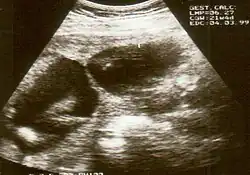

![]() | |

| An infant's hand affected by constriction ring syndrome | |

Diagnosis of constriction ring syndrome can be confirmed with an ultrasonography. The clinical manifestations can be extremely variable. It could be a single or multiple manifestation. This can be confirmed at the end of the first trimester or at the beginning of the second trimester.[13] However, not every patient will be diagnosed at that moment; most will be diagnosed at birth.

Individual strands are small and hard to see on ultrasound, so bands are detected indirectly because of the constrictions and swelling upon limbs or digits. Misdiagnosis is also common, so if there are any signs of amniotic bands, further detailed ultrasound tests should be done to assess the severity. 3D ultrasound and MRI can be used for more detailed and accurate diagnosis of bands and the resulting damage/danger to the fetus.